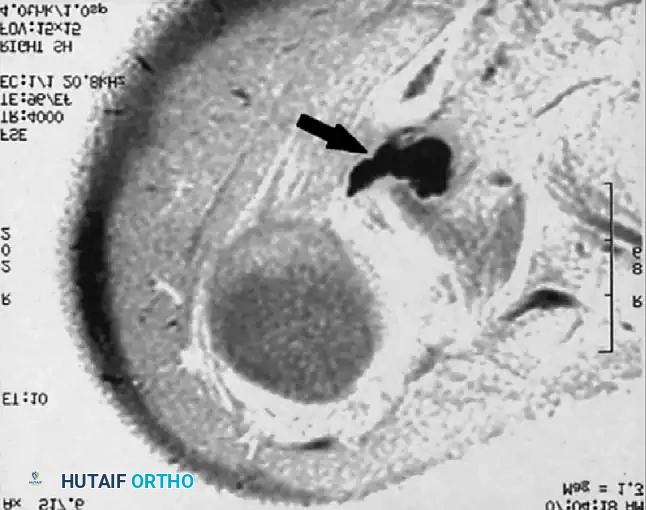

Associated Surgical & Radiographic Imaging